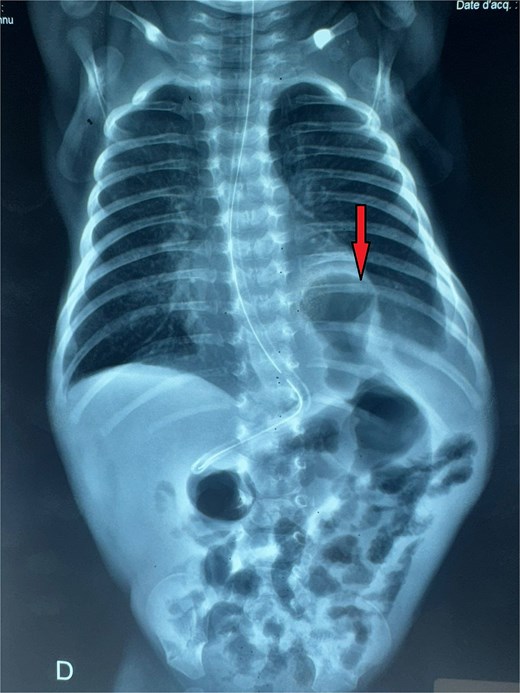

A male neonate was admitted at 47 h of life with signs of severe respiratory distress requiring immediate intubation. Physical examination revealed a distended abdomen, a prominent thoracic contour, and diminished breath sounds on the left side. A thoraco-abdominal X-ray showed multiple air-filled intestinal loops in the left hemithorax, consistent with a CDH. The patient underwent a primary repair of surgical repair of his diaphragmatic defect (Fig. 1). The initial postoperative course was complicated by multiple episodes of bowel obstruction. Postoperative radiographs demonstrated multiple air-fluid levels without evidence of significant colonic dilatation (Fig. 2). The patient underwent reoperations on postoperative days 21 and 50. Intraoperative findings revealed early adhesions without evidence of other anomalies. Adhesiolysis was performed on both occasions. The patient was discharged on postoperative day 60. At 3 months of age, the child was readmitted with signs of recurrent intestinal obstruction, including bilious vomiting, absence of stool and gas passage, and abdominal distension. The mother reported that spontaneous bowel movements occurred only after the administration of suppositories. Additionally, the child exhibited failure to thrive, with a weight below −2 standard deviations for age. The child had no facial dysmorphism or abnormalities of the limbs or nails.

Postoperative abdominal radiograph demonstrating multiple air-fluid levels (arrows) without evidence of significant colonic dilatation.